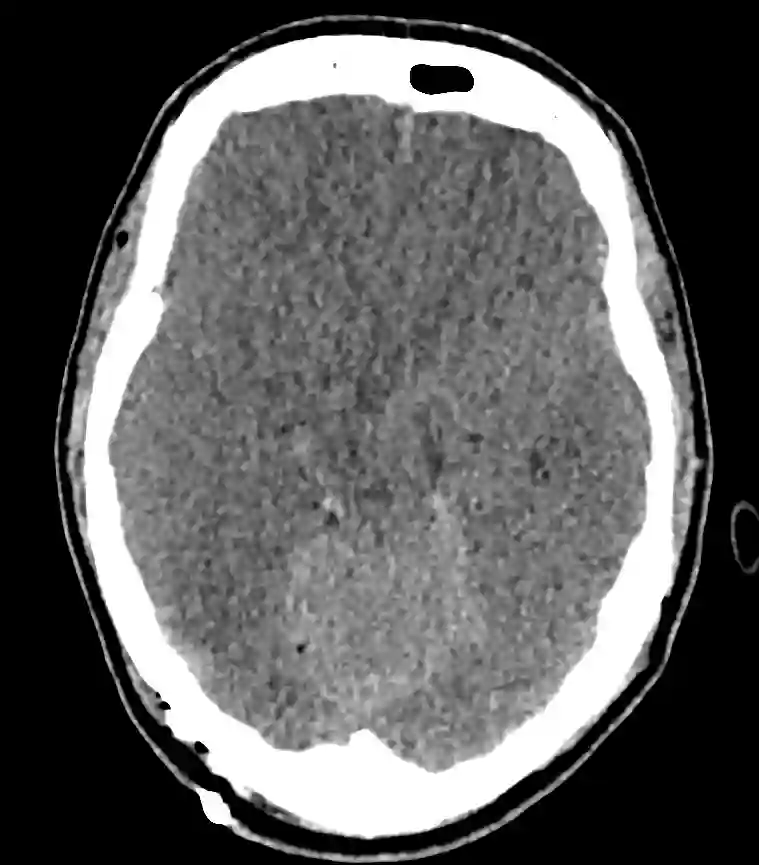

Axiales CT Bild eines Patienten mit einem generalisierten Hirnödem, verstrichenen Rinden-Markgrenzen und verstrichenen basalen Zisternen.

Generalisiertes Hirnödem CT